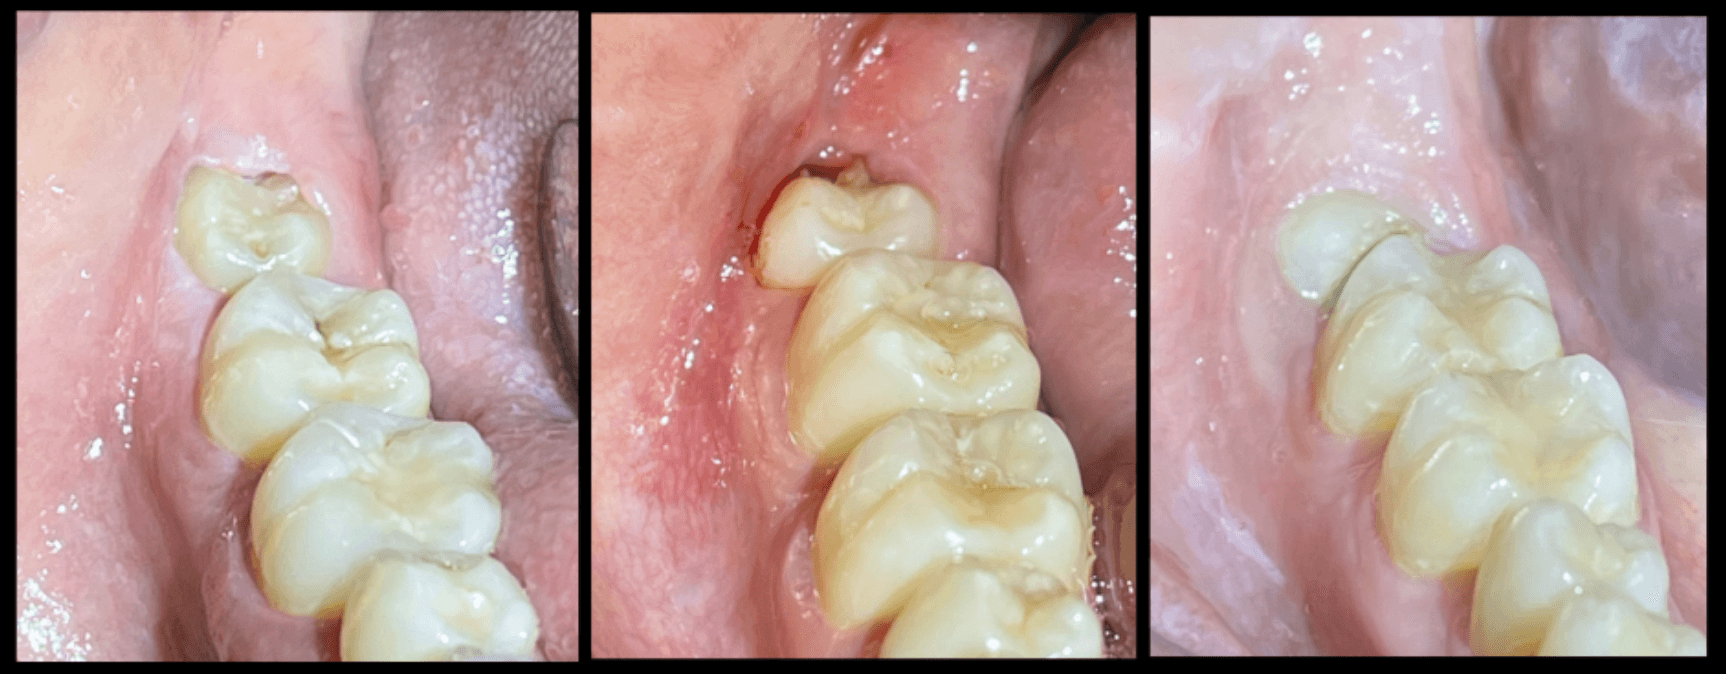

즉시 보철 임플란트

수술 당일, 임시 치아까지 완성하여 바로 일상생활이 가능합니다.

즉시 보철 임플란트는 임플란트 수술 후 잇몸이 아물기를 기다렸다가 보철물을 연결하는 기존 방식과 달리,

임플란트 식립과 동시에 임시 보철물(임시 치아)을 연결하여 바로 외모 개선 및 제한적인 저작 기능을 회복할 수 있도록 하는 치료 방법입니다.

즉시 보철 임플란트의 장점

치료 기간 대폭 단축: 여러 번 내원 NO

즉각 심미성 회복: 앞니 결손도 당일 커버

기능 유지: 부드러운 음식·발음 가능

잇몸 라인 보존: 자연스러운 최종 결과

수술 횟수↓: 발치·식립·임시 치아를 원스톱으로

하루면 끝! 즉시 보철 임플란트로 당일에 자신감과 생활 편의를 동시에 누리세요.